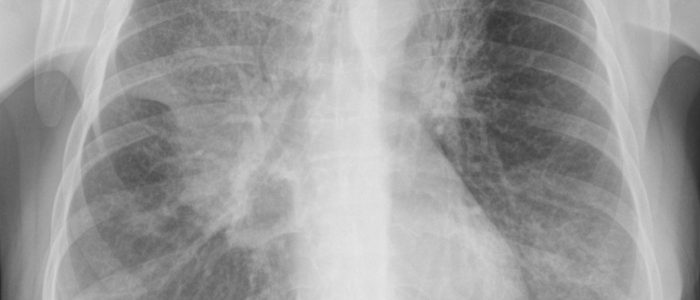

При обследовании пациента врач сначала врач осматривает пациента, составляет анамнез. Чтобы обнаружить образование пациента направляют на флюорографию, бронхоскопию, биопсию, рентгенологическое исследование и компьютерную томографию. Когда опухоль не сопровождается неприятными признаками, а человек чувствует себя нормально, в операции нет необходимости. Но за человеком постоянно наблюдают, чтобы новообразование не приобрело злокачественный характер. При появлении у пациента патологических признаков, жировик удаляют хирургическим путем.